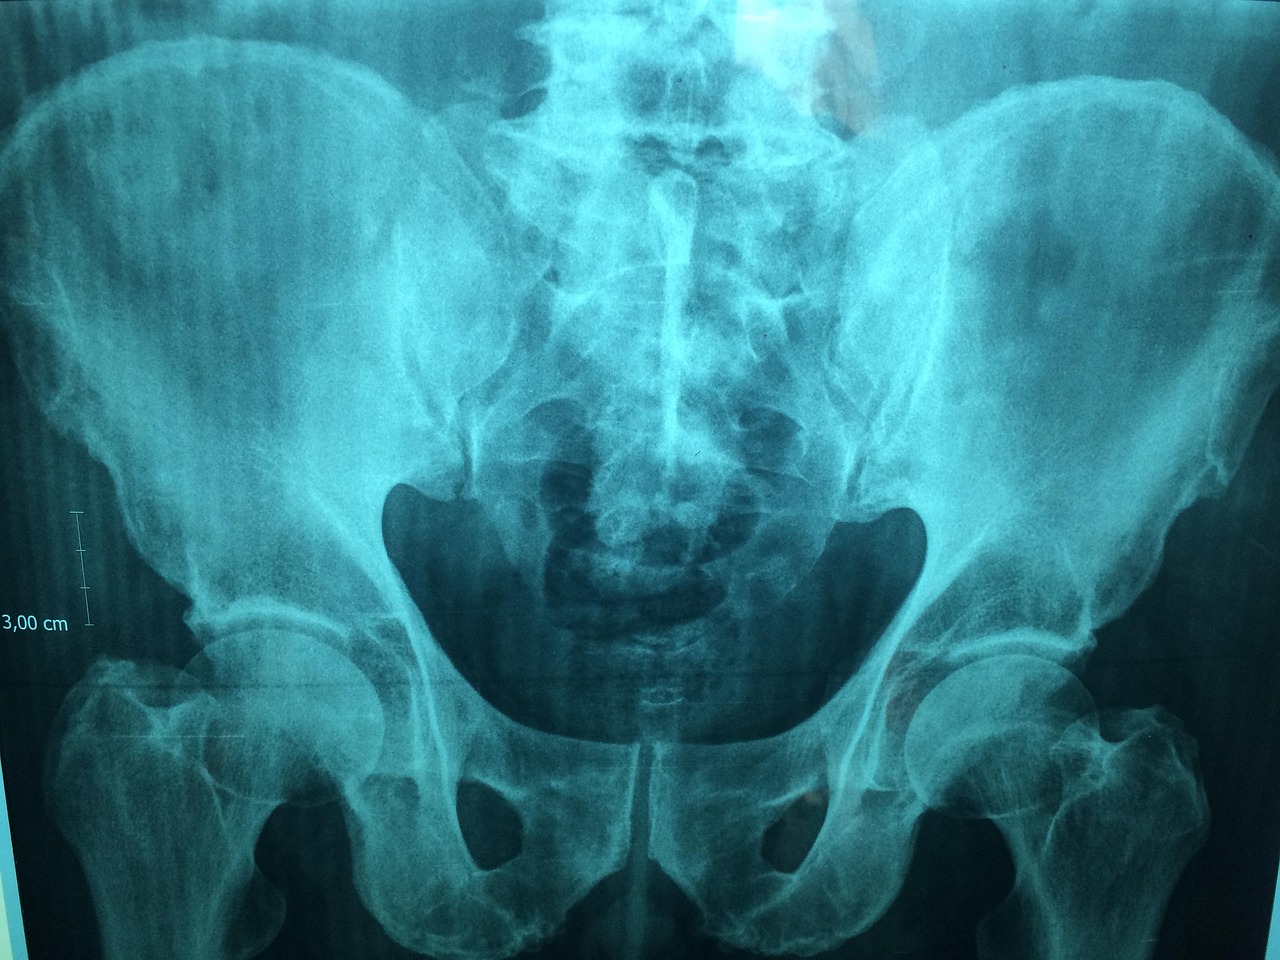

骨骼不仅是支撑身体结构的框架,更是参与多种生理功能的关键器官,如矿物质代谢、血液生成及免疫调节等,随着年龄的增长,骨骼中的钙质和骨密度逐渐流失,导致骨质疏松和骨折风险增加,据世界卫生组织(WHO)数据,全球约有1/3的女性及1/5的男性在50岁后将面临骨质疏松性骨折的风险,这不仅严重影响患者的生活质量,还带来巨大的经济负担,加强骨骼健康研究,预防和治疗骨骼疾病,对于提升全球人口健康水平具有重要意义。